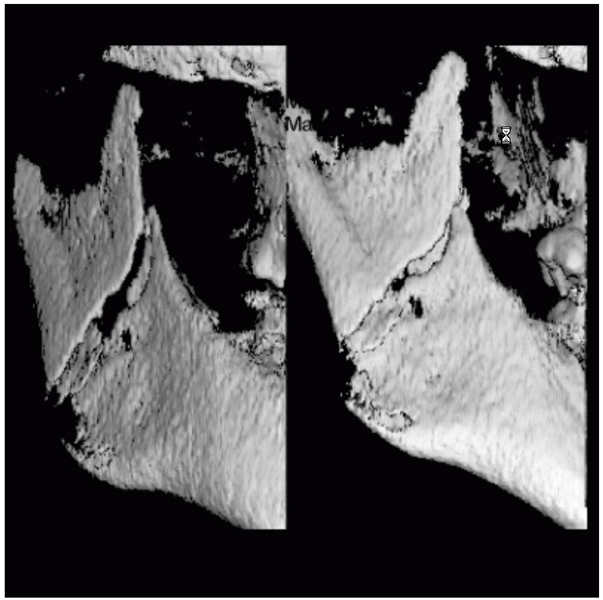

Je speciální zubní digitální tříprostorový tomograf (3D), který umožňuje na základě jediného snímkování vytvořit všechny typy RTG zobrazení, které jsou pro lékaře potřebné. Díky používané technologii tzv. „kuželového paprsku“ a speciálním senzorům je výrazně zmenšená dávka záření - o více jak 80% proti klasickému CT vyšetření. To je významné zejména u dětí. Pomocí tohoto přístroje je možné zjisti skutečnou situaci v čelistních kostech pacienta tedy množství kosti - můžeme změřit skutečnou šířku i výšku kosti, i kvalitu kosti (hustotu) v místě uvažované implantace. 3D (tříprostorové) zobrazení umožňuje zvýšit prostorovou představu operatéra ještě před vlastní operací a zároveň pacientovi lépe objasnit a ukázat oblast plánovaného zavedení implantátu.

Pacient „neumí číst“ RTG snímky, ale díky 3D zobrazení vidí „svoji skutečnou čelist“ - např. jak je nízká či úzká, vidí průběh nervu nebo velikost čelistní dutiny, což mu umožní i pochopení nutnosti v některých případech provést pomocné zákroky ještě před vlastním zavedením implantátu (viz. kostní štěp, sinus lift, kostní granulát...).

Vyšetření pomocí tohoto přístroje používáme i ve stomatochirurgii (zlomeniny čelistí, zuby moudrosti, cysty, onemocnění čelistního kloubu), ortodoncii (retinované zuby, nadpočetné zuby), parodontologii atd.